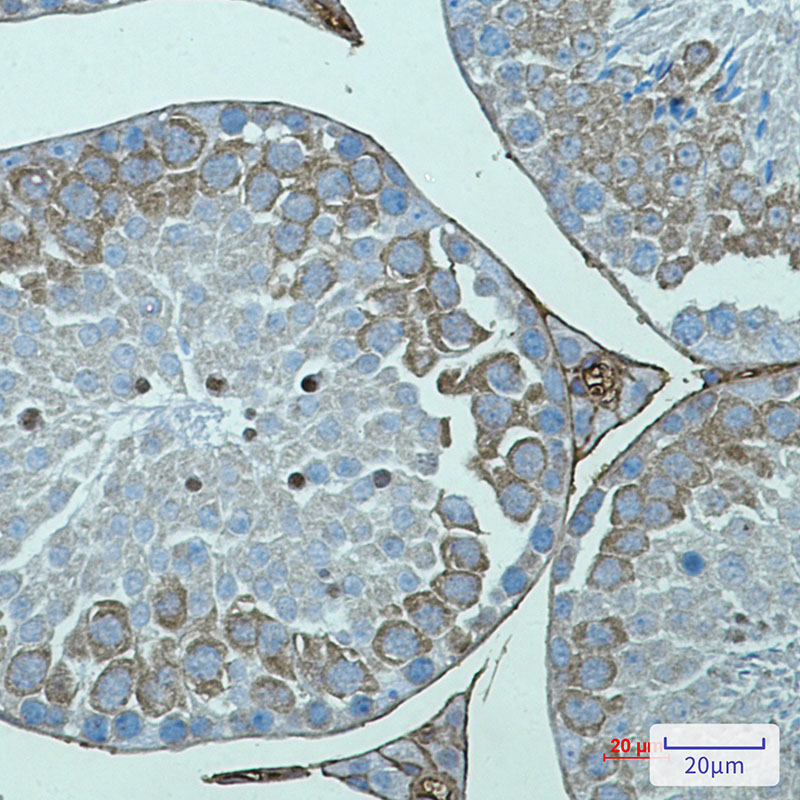

Product Image

IHC | 1/50-1/100 |